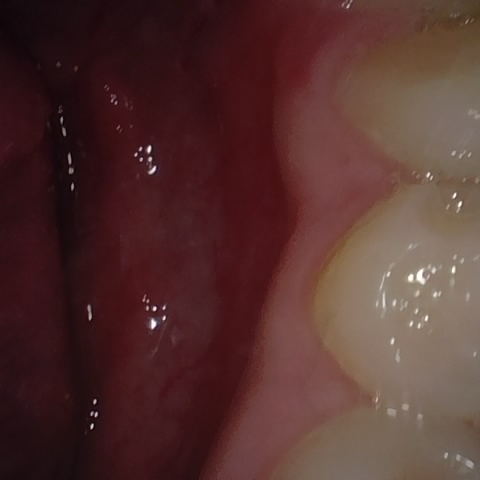

NHD20738

Annotated as "Good"